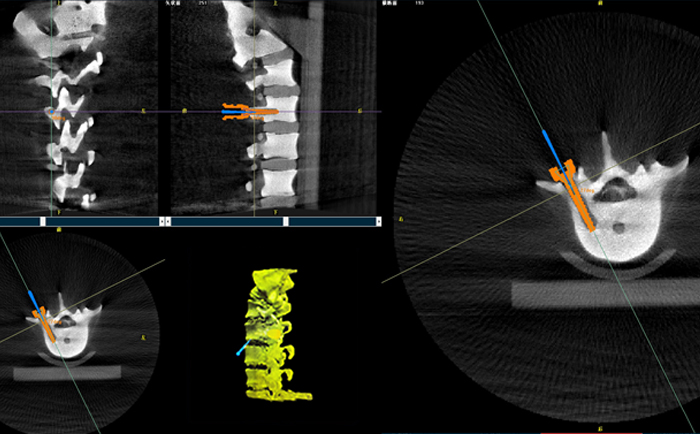

在一臺(tái)機(jī)器人輔助下的脊柱手術(shù)中,使用三維C形臂與機(jī)器人匹配,僅15秒左右就能獲得患者病變脊柱部位的高清3D圖像,機(jī)器人輔助手術(shù)可準(zhǔn)確定位病變部位、置入椎弓根螺釘位置等。

目前脊柱外科應(yīng)用最廣泛的還是機(jī)器人輔助置入椎弓根螺釘。主刀大夫可以通過(guò)該3D圖像確定手術(shù)中椎弓根螺釘?shù)倪M(jìn)釘點(diǎn)、置釘方向以及置釘深度。緊接著,在機(jī)器人手術(shù)系統(tǒng)的導(dǎo)航下,該機(jī)械手臂能夠準(zhǔn)確移動(dòng)到定位椎弓根螺釘?shù)戎冕斘恢茫t(yī)生只需要在置釘部位切開(kāi)一個(gè)1cm切口,沿著機(jī)械臂所指方向鉆入導(dǎo)針,并沿導(dǎo)針按置入椎弓根即可,從而使椎弓根螺釘能夠以最理想化的方式打入,保證患者的安全和手術(shù)有效性。